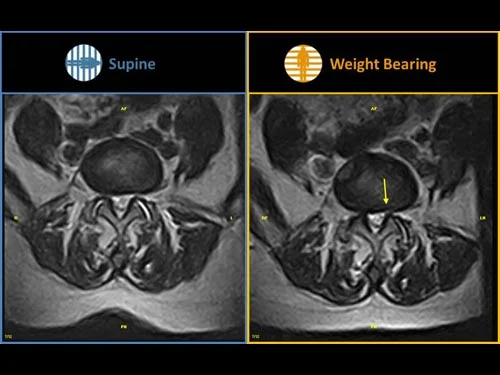

이렇게 신경근에 대한 압박이 없는 환자라도 체중이 실린 상태에서 MRI 촬영을 한다면 신경을 압박하게 될 수도 있습니다.

물론 일반적인 protrusion, extrusion 환자들도 서서 촬영시에 디스크 탈출량이 늘어나고 신경압박의 정도가 심했겠지요?